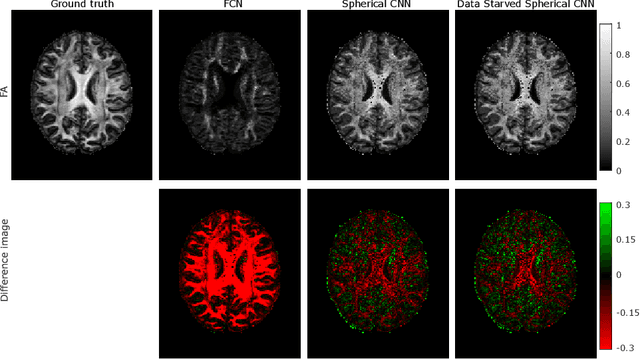

This paper demonstrates spherical convolutional neural networks (S-CNN) offer distinct advantages over conventional fully-connected networks (FCN) at estimating scalar parameters of tissue microstructure from diffusion MRI (dMRI). Such microstructure parameters are valuable for identifying pathology and quantifying its extent. However, current clinical practice commonly acquires dMRI data consisting of only 6 diffusion weighted images (DWIs), limiting the accuracy and precision of estimated microstructure indices. Machine learning (ML) has been proposed to address this challenge. However, existing ML-based methods are not robust to differing dMRI gradient sampling schemes, nor are they rotation equivariant. Lack of robustness to sampling schemes requires a new network to be trained for each scheme, complicating the analysis of data from multiple sources. A possible consequence of the lack of rotational equivariance is that the training dataset must contain a diverse range of microstucture orientations. Here, we show spherical CNNs represent a compelling alternative that is robust to new sampling schemes as well as offering rotational equivariance. We show the latter can be leveraged to decrease the number of training datapoints required.